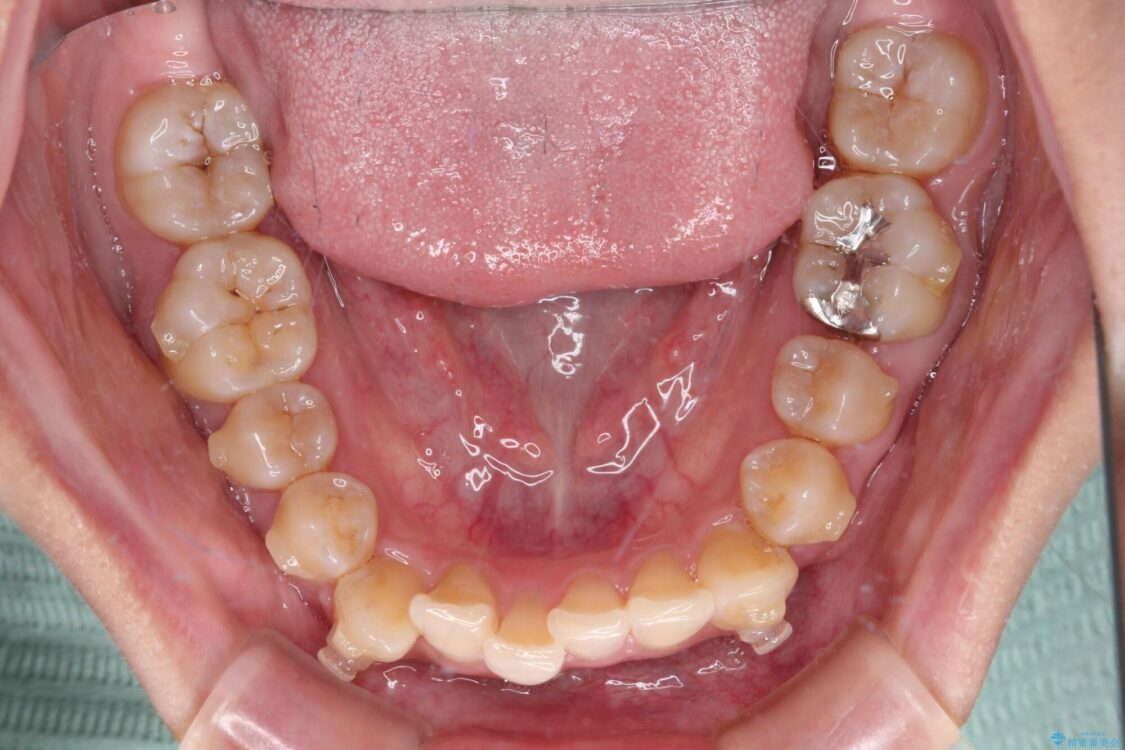

下顎の八重歯を気にして来院された患者様です。

下顎前歯にデコボコが集中していたため、顎間ゴムによる後方移動とIPR(歯と歯の間を削ること)により歯列を整えることとしました。

治療前、下顎前歯のデコボコが集中しており、奥歯の咬み合わせは、上顎に対して下顎が前方位にある状態でした。下顎の歯列を後方へ移動させる治療はインビザラインの得意とするところですので、1年程度で無事に治療を終えることができました。

治療前

• 【モニター】下顎前歯のデコボコをインビザラインできれいに 治療前画像